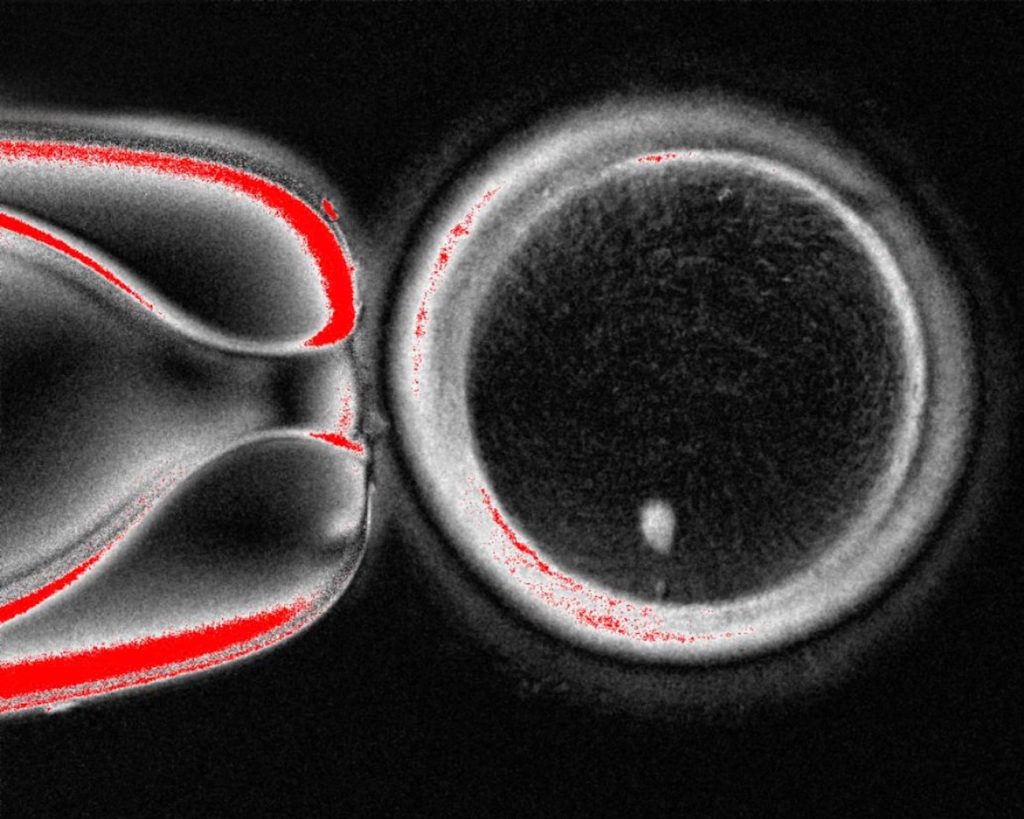

براساس گزارش BBC، روش محققان دانشگاه بهداشت و علوم اورگان داستان ساده لقاح را بهکلی تغییر میدهد. فرایند جدید در چند مرحله پیچیده انجام میشود: ابتدا، محققان هسته یک سلول پوست را که حاوی مجموعه کامل ۴۶ کروموزوم فرد است، خارج میکنند. سپس، این هسته را به یک تخمک اهدایی که هسته خودش از آن خارج شده، منتقل میکنند؛ روشی که یادآور تکنیک استفادهشده برای شبیهسازی گوسفند معروف، «دالی»، است.

اما این تخمک هنوز آماده لقاح نیست، زیرا ۴۶ کروموزوم دارد، درحالیکه یک تخمک سالم باید ۲۳ کروموزوم داشته باشد. در مرحله بعدی، دانشمندان با استفاده از یک ترکیب شیمیایی تخمک را وادار میکنند تا نیمی از کروموزومهای خود را بهصورت تصادفی دور بریزد. پس از این مرحله، تخمک مصنوعی با ۲۳ کروموزوم آماده است تا با اسپرم بارور شود.